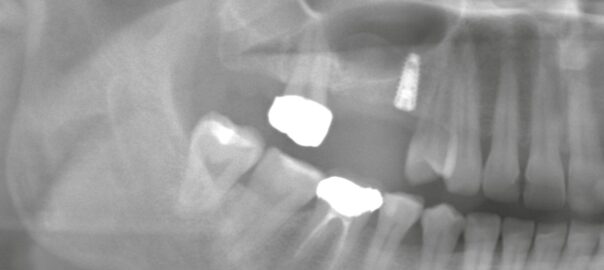

- 2025/09/03 右上欠損に対するインプラントプランニング

こんにちは。静岡市駿河区の小嶋デンタルクリニックです。 本日は「右上の欠損部に対するインプラント治療のプランニング」についてご紹介します。 欠損部の状態とリスク 右上の欠損部をパノラマ撮影にて確認したところ、上顎洞との著 … 続きを読む 右上欠損に対するインプラントプランニング